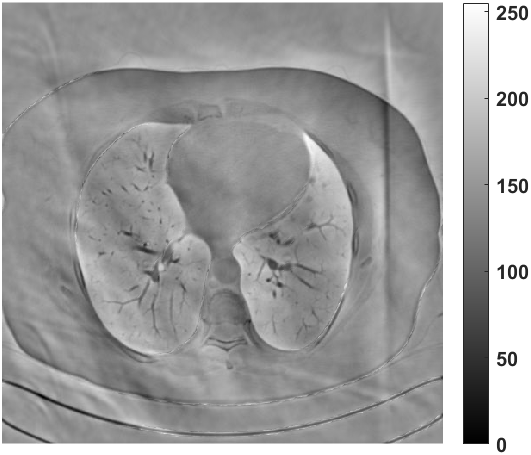

Fig. 4 presents the reconstruction results and residual images obtained by different methods for limited-angle reconstruction. As can be seen, the learning-based methods outperform the direct method and TV model, which exhibit serious artifacts in the missing angle region. Although the denoiser introduced by the FBP-Unet can somehow deal with the noises, the result still presents obvious artifacts. Compared to the SIPID, PD-net and FSR-nets, our LRIP-net1/2 can better preserve the image details and edges with less information left in the residual images. Thus, both the quantitative and qualitative results confirm that the low-to-high double-resolution strategy can improve the reconstruction accuracy for the limited-angle reconstruction problem.

We observe that the low-resolution image prior plays an important role in our method. More specifically, we compare the results of our LRIP-net with respect to different low-resolution priors, which are obtained by down-sampling rate of 1/2, 1/4, and 1/8, respectively. As can be seen in Table III, the best reconstruction results are obtained with the image prior reconstructed by the down-sampling rate of for 150∘, 120∘ and 90∘ limited-angle reconstruction. The visual comparison based on different image priors are also provided in Fig. 5, where obviously less artifacts are left in the reconstruction image by LRIP-net1/8. By comparing the running time, it is easy to see that the smaller the low-resolution image prior, the faster the LRIP-net works.